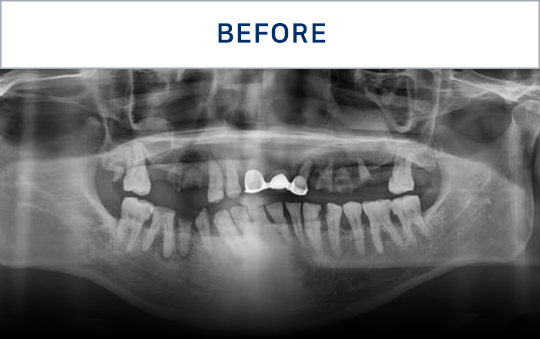

전후가 명확한 결과, 그 결과가

곧 신길플란트치과의 신뢰입니다.